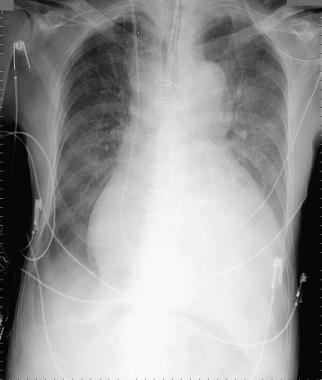

A pericardial effusion ( Figs. 16-1 to 16-15 ) is often suggested on the frontal chest radiograph by a smoothly distended, “flasklike” CPS. More than 500 mL of fluid must be present before the change in the CPS is fairly obvious. A flasklike appearance may be caused by myocardial disease as well; scrutiny of the hilar vessels may distinguish the two. In the presence of pericardial effusion, the hilar vessels are covered (the pericardium runs up onto them and obscures them). In the presence of myocardial disease, the hilar vessels are unusually prominent as they are distended under higher than usual pressure.

In a minority of patients with pericardial effusion, on the lateral radiograph, a stripe of radiolucent epicardial fat, a “fat line,” may be visible anteriorly, suggesting fluid in the pericardial space. A stripe greater than 2 mm is abnormal. This “pericardial stripe sign” is more easily seen in adults than children (more fat!).

A prominent azygous vein, superior vena cava, or inferior vena cava suggests cardiac tamponade.

Echocardiography is the diagnostic test of choice for the evaluation of pericardial effusions. Pericardial tamponade remains a clinical diagnosis, strengthened by supportive echocardiographic findings.